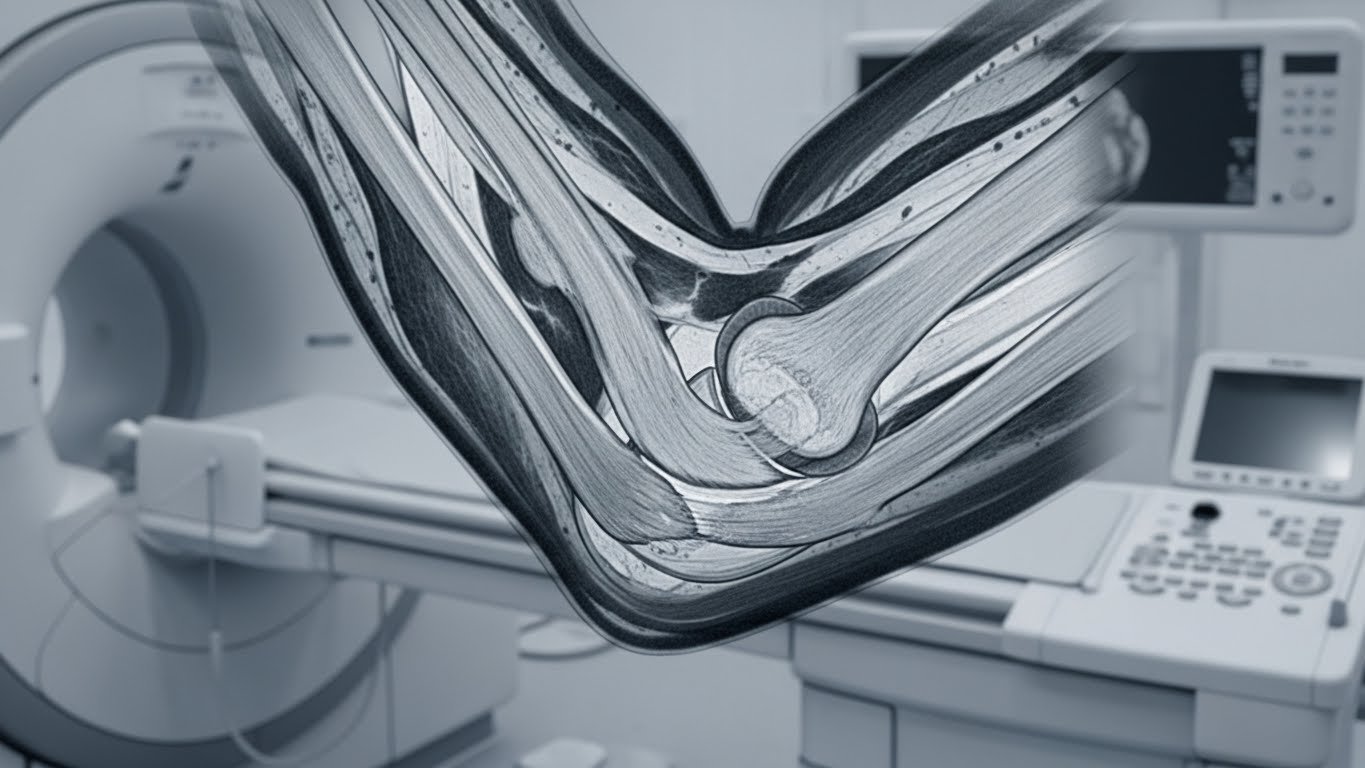

L’IRM (Imagerie par Résonance Magnétique) du coude est un examen radiologique de référence qui permet de visualiser avec précision les structures internes de votre articulation : os, tendons, ligaments, cartilage et nerfs. Contrairement à la radiographie standard, l’IRM n’utilise aucune radiation et offre des images détaillées indispensables au diagnostic de nombreuses pathologies.